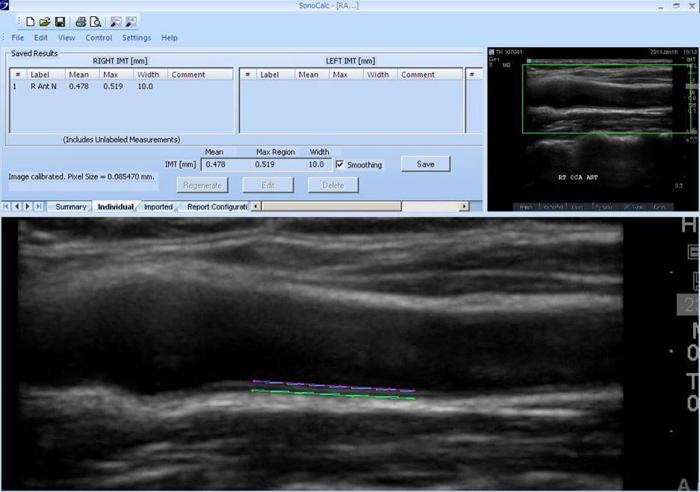

In this multi-centric study, 1229 subjects with age ≥30 years and no previous cardiovascular disease (CVD) underwent CVD risk factor assessment and CIMT measurement. Mean far wall common carotid artery IMT was measured on both sides and averaged.

方法

在这项多中心研究中,1229名年龄≥30岁且既往无心血管疾病(CVD)的受试者接受了CVD危险因素评估和CIMT测量。测量双侧颈总动脉远壁的平均IMT并取平均值。